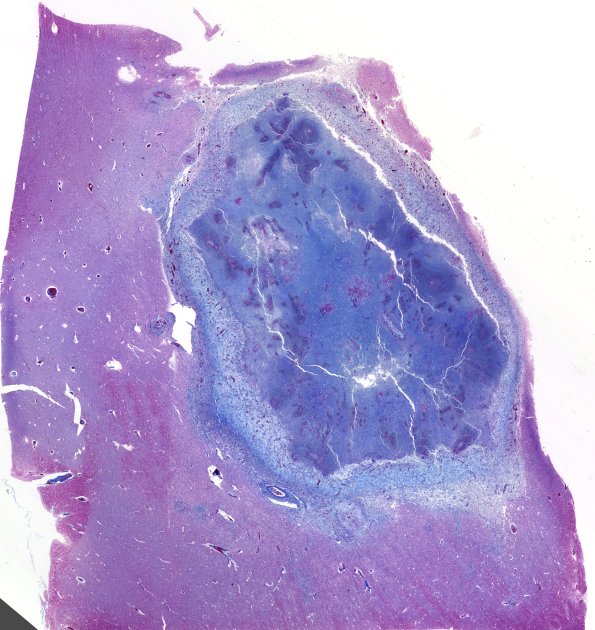

Washington University Experience | INFECTION | Fungus | Mucormycosis - Zygomycosis | 12H Abscess (Case 12) N4 TRI WM

The external abscess collagenous wall stains strongly with Trichrome. ---- Comment: We were suspicious of a bacterial component in these lesions. Bacteria are well stained with GMS but the only elements discerned in the clouds of PMNs were crumbs of necrotic debris, too large for bacteria and too small for other fungal species. A Gram stain provided no resolution of this question.